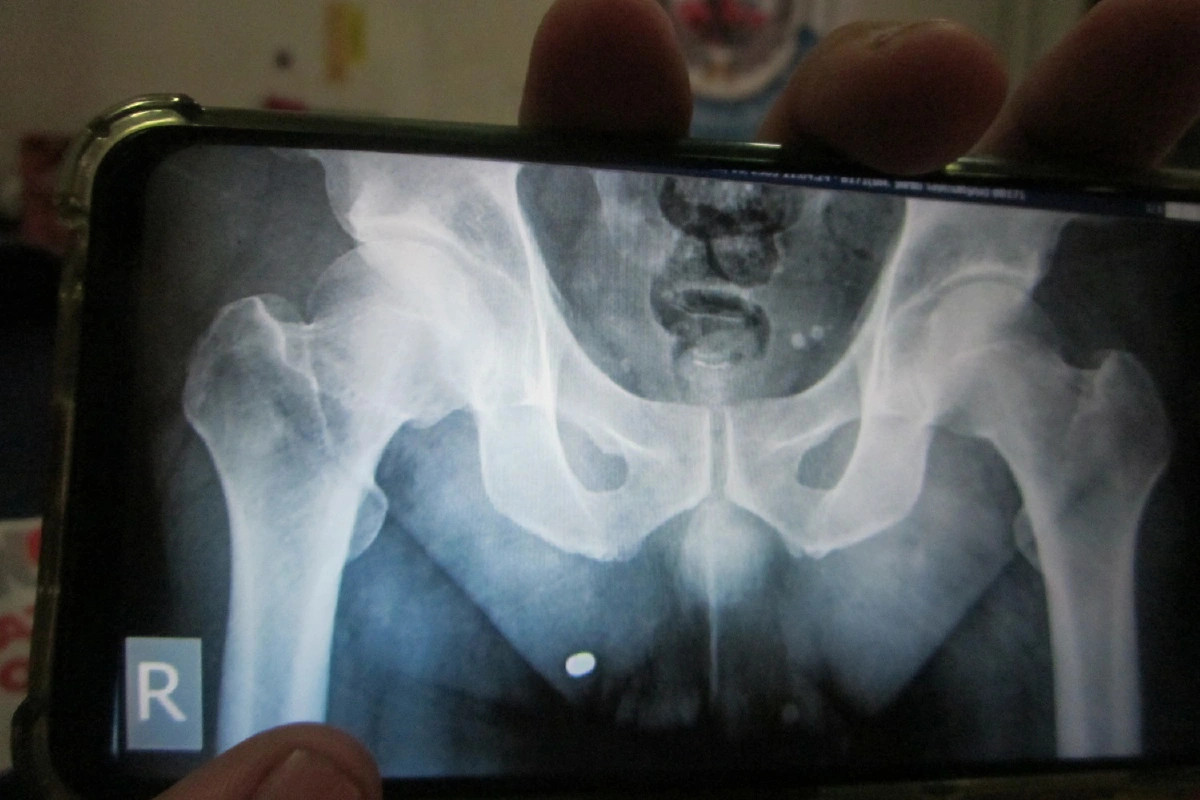

มีการขยายความเรื่องนี้ผ่านโลกออนไลน์ เจ้าตัวถูกกระสุนฝังร่างมานานกว่า 5 เดือน แต่ทำไมจากคดีพยายามฆ่าถึงกลายเป็นแค่พกพาอาวุธปื เกิดข้อกังขาถึงการทำคดี